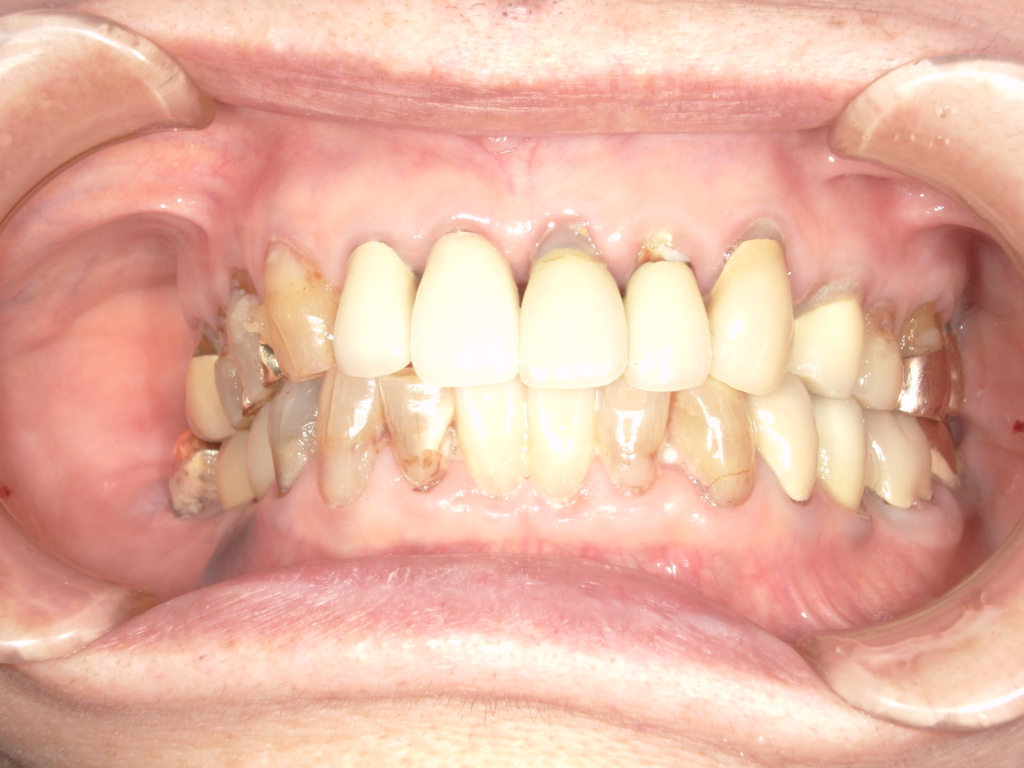

Y様インプラント実例 #44

左の上下の奥歯をインプラントで治療しています。

左下の奥歯は歯を抜くのと同時にインプラントの埋め込みを行っています。

被せものは上下、セラミックスで作っています。

治療前

治療後